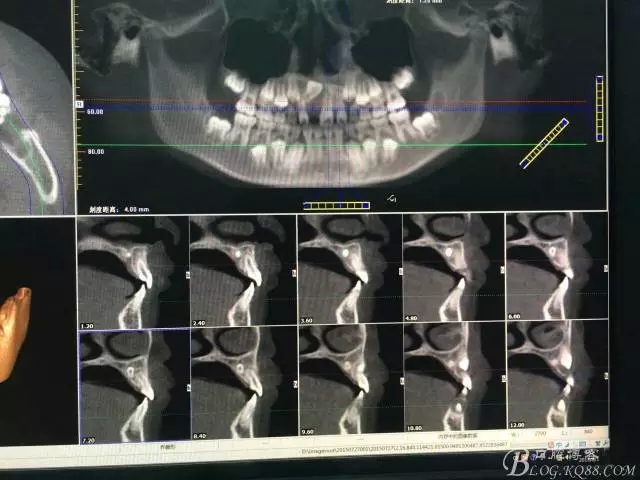

圖1.術(shù)前CBCT檢查:11牙冠90°唇側(cè)傾斜,21和22根尖區(qū)腭側(cè)有一埋伏多生牙